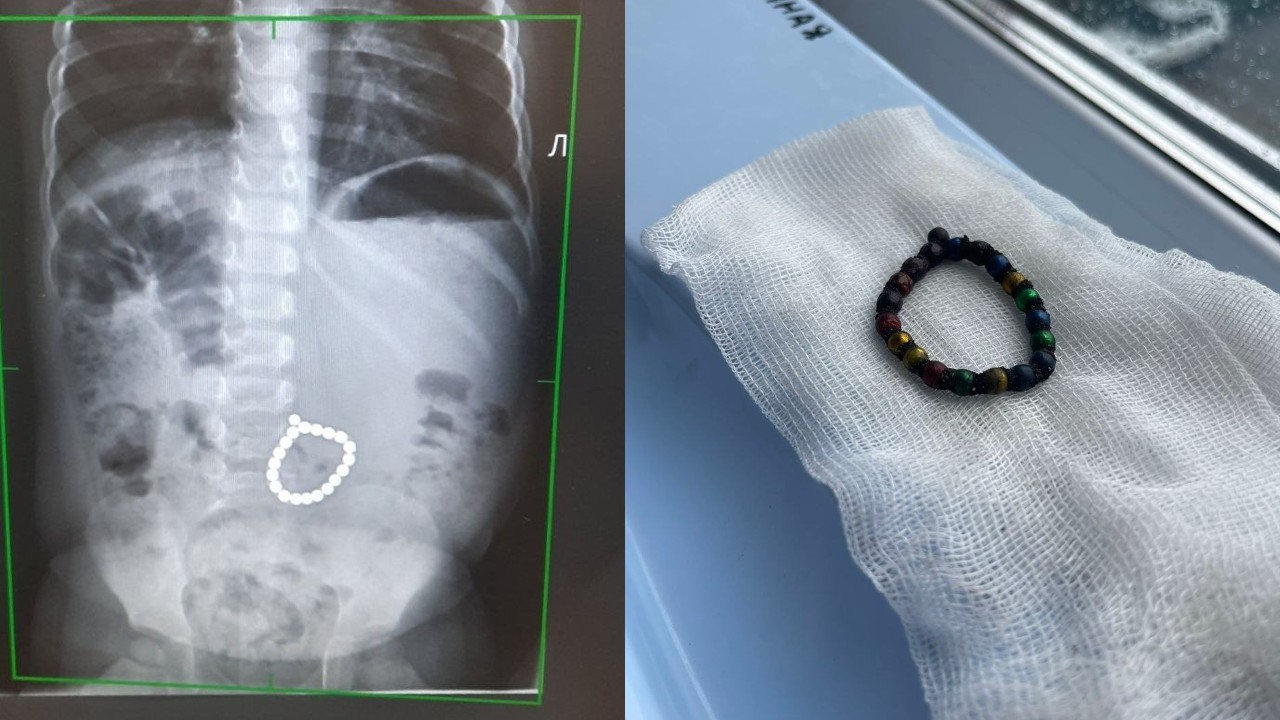

Магнитные шарики на рентгене: Интересные находки

Раздел: Картинки на заметку